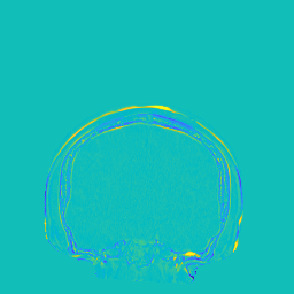

Model-based treatment planning for transcranial ultrasound therapy typically involves mapping the acoustic properties of the skull from an x-ray computed tomography (CT) image of the head. Here, three methods for generating pseudo-CT images from magnetic resonance (MR) images were compared as an alternative to CT. A convolutional neural network (U-Net) was trained on paired MR-CT images to generate pseudo-CT images from either T1-weighted or zero-echo time (ZTE) MR images (denoted tCT and zCT, respectively). A direct mapping from ZTE to pseudo-CT was also implemented (denoted cCT). When comparing the pseudo-CT and ground truth CT images for the test set, the mean absolute error was 133, 83, and 145 Hounsfield units (HU) across the whole head, and 398, 222, and 336 HU within the skull for the tCT, zCT, and cCT images, respectively. Ultrasound simulations were also performed using the generated pseudo-CT images and compared to simulations based on CT. An annular array transducer was used targeting the visual or motor cortex. The mean differences in the simulated focal pressure, focal position, and focal volume were 9.9%, 1.5 mm, and 15.1% for simulations based on the tCT images, 5.7%, 0.6 mm, and 5.7% for the zCT, and 6.7%, 0.9 mm, and 12.1% for the cCT. The improved results for images mapped from ZTE highlight the advantage of using imaging sequences which improve contrast of the skull bone. Overall, these results demonstrate that acoustic simulations based on MR images can give comparable accuracy to those based on CT.